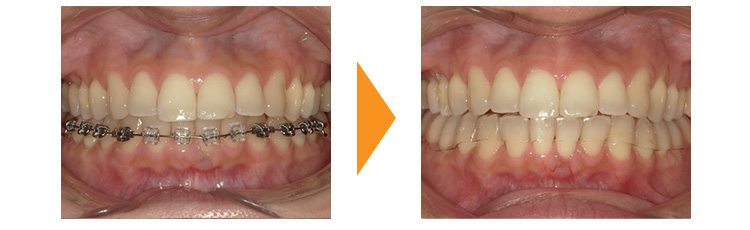

子供の時に矯正治療を行っていた患者様です。矯正後は並んでいたが、矯正治療後2年経過した段階で保定装置(リテーナー)を除去し、親知らずをぬいていなかったため前歯のガタガタが戻ってしまったとのことでした。

幸い奥歯の噛み合わせなどには問題なかったため、下顎のみの部分的な矯正治療で対応できました。

親知らずの存在と保定装置を撤去したことが後戻りの原因であるため、矯正中に親知らずを抜歯していただき、保定装置は取り外しのできない舌側固定は半永久的に使用し、取り外し式のマウスピースも夜間は必ずしていただく必要があることを事前に説明し矯正治療を行いました。

矯正治療は並べて終わりではありません。矯正後は保定・維持の始まりでもあります。歯並びによっては保定装置の使用が必要ない場合もありますが、基本的には長期間の保定装置の使用が望ましいことをよくご理解いただけたらと思います。